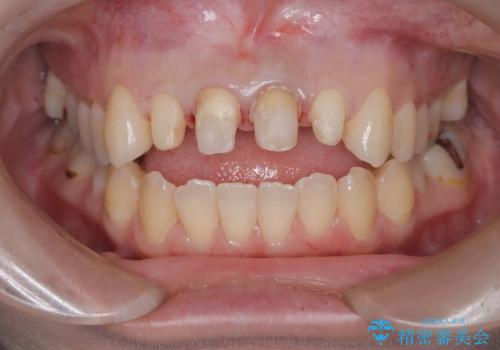

- 「前歯の色が気になる」を主訴に来院された患者様です。前歯が咬んでない開咬という状態のため、矯正治療を勧めましたが、患者様がご希望されなかったためオールセラミッククラウンで治療を行いました。右上1番は、神経の検査の結果、神経が死んでいたため根管療から行いました。左上1番は、金属の土台が入っていたのとラバーダムシートを使用せず根管治療が行われていたため、再度根管治療から行いました。その後ファイバーコアをたてオールセラミッククラウンで治療を行いました。

- 66万円(仮歯1万1千円×4 ファイバーコア2万2千円×2 オールセラミッククラウン スペシャル14万3千円×4)費用は治療当時の料金となります

※今後ホワイトニングを行う予定なので患者様の希望により少し被せ物を白くしています。